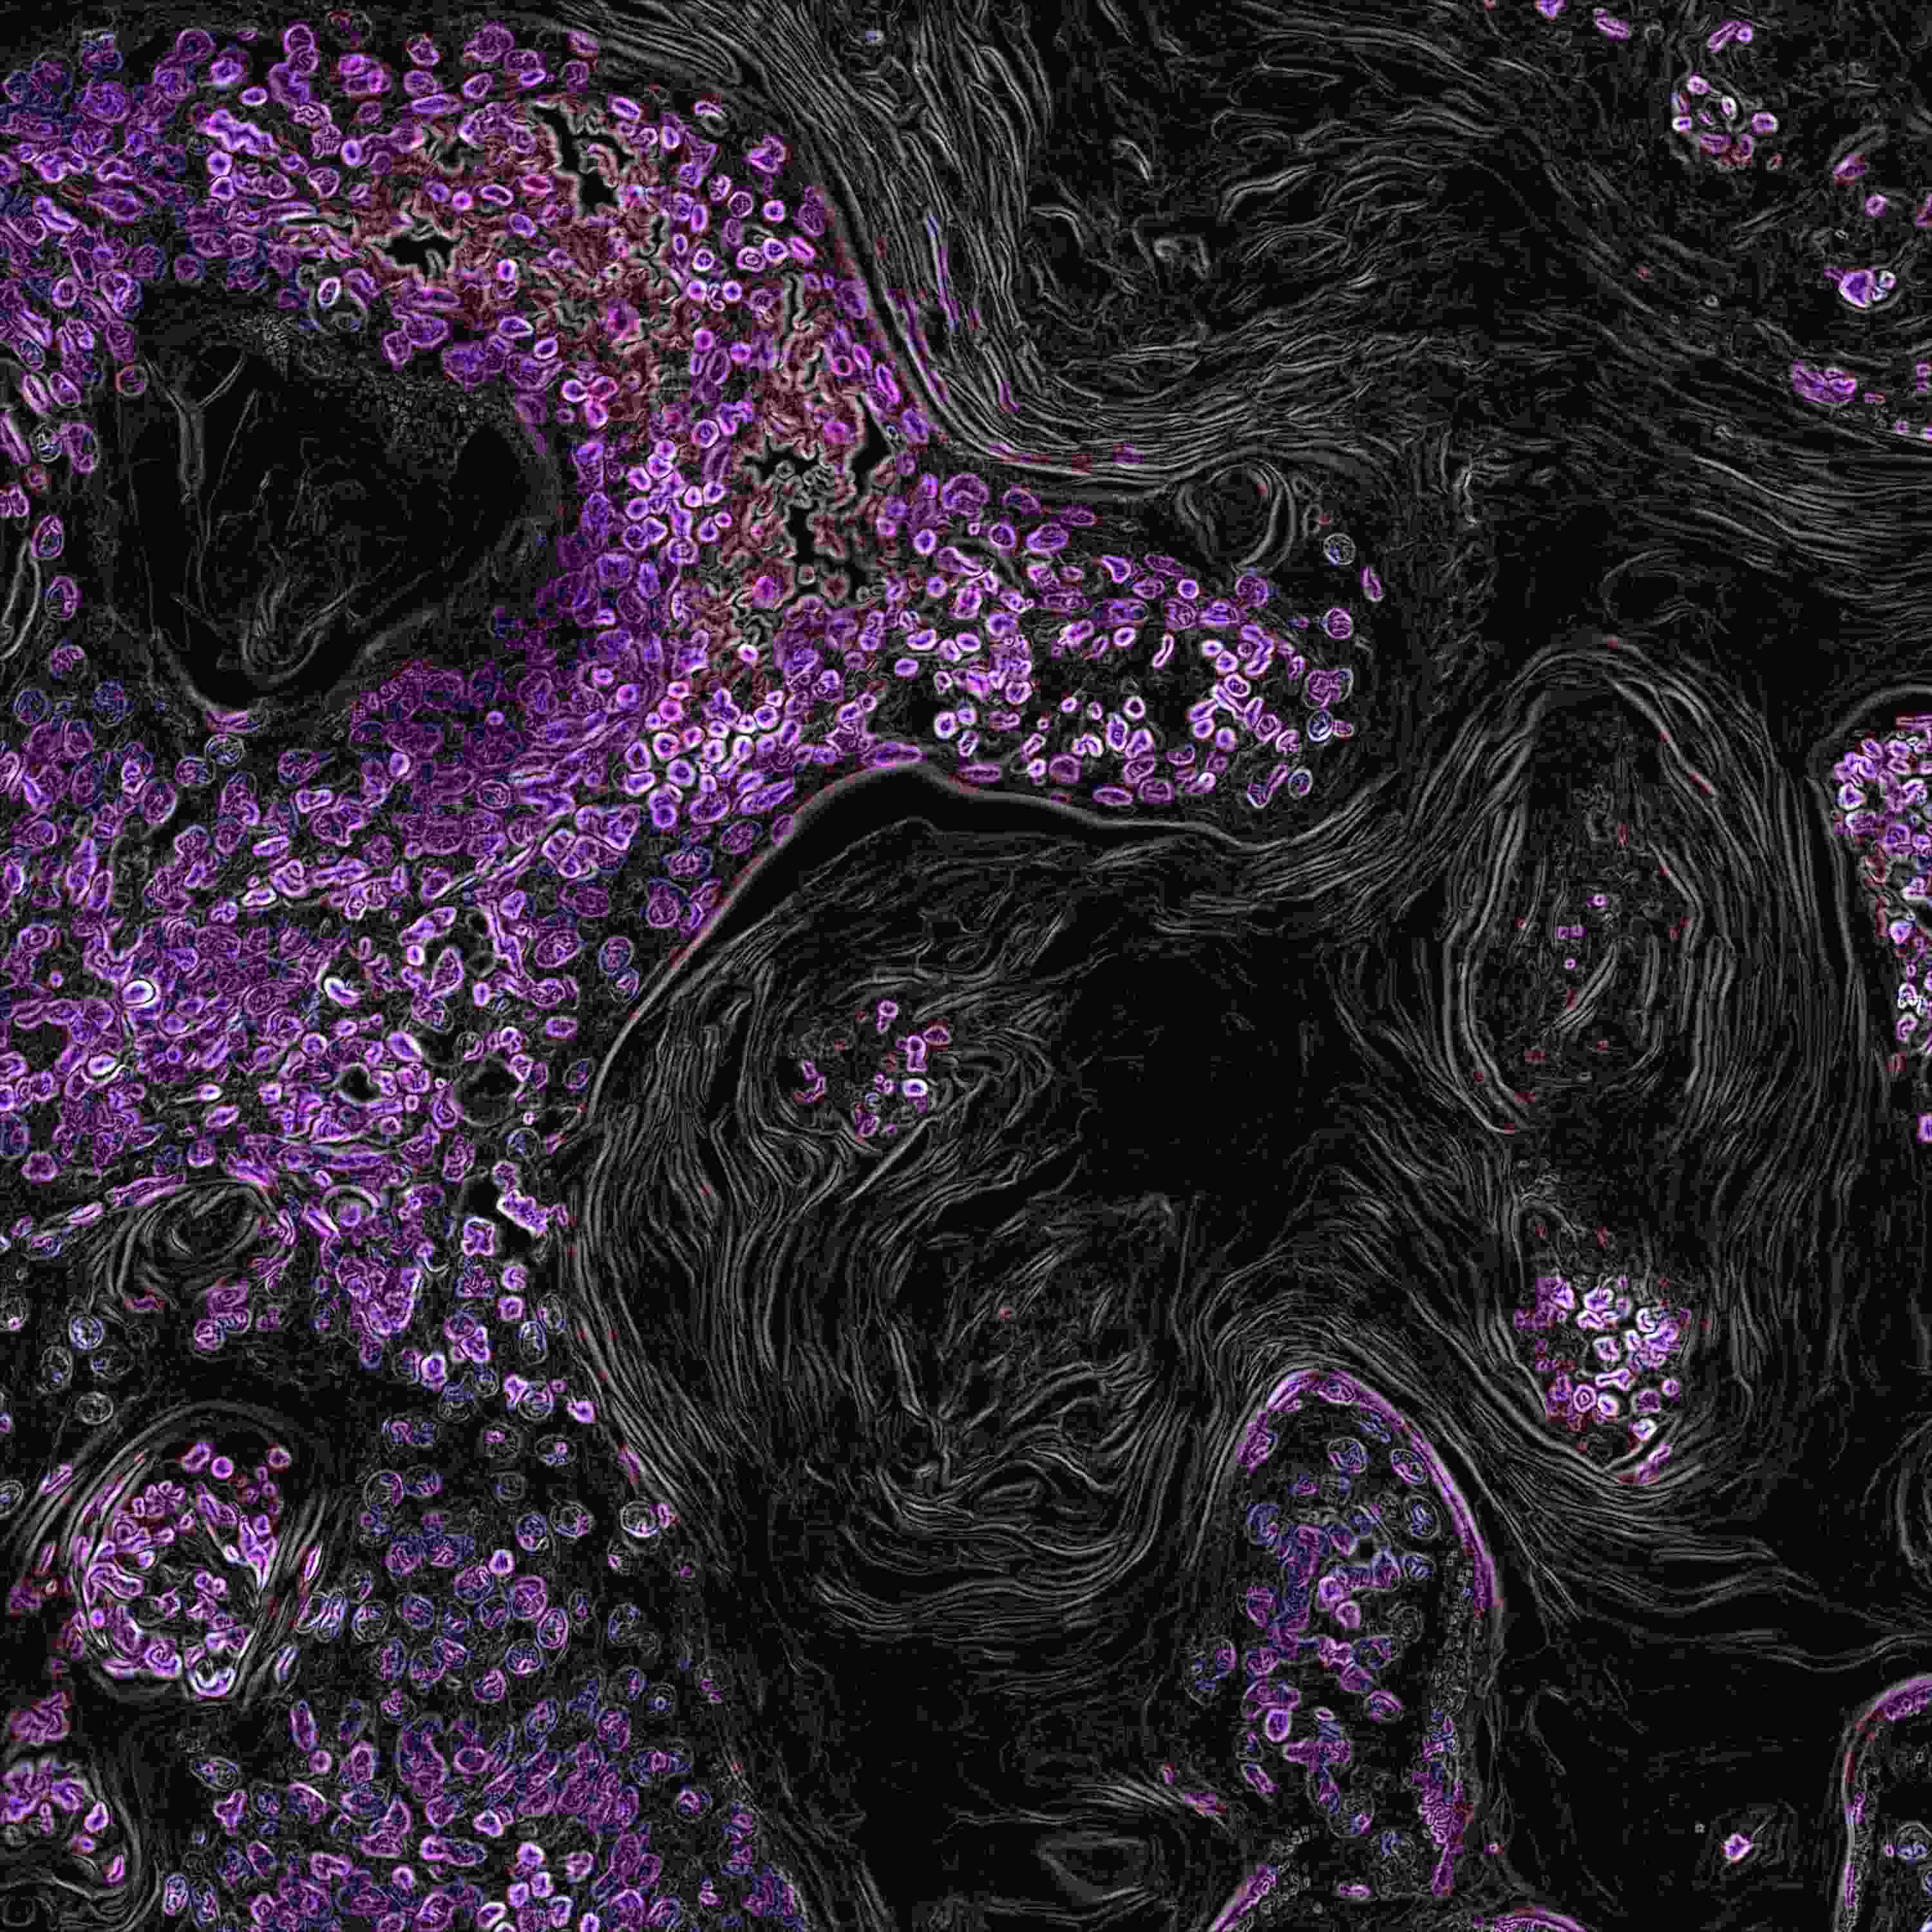

Our generics portfolio encompasses oral oncology and key therapeutic areas including CNS, oncology and immunology, primary care and lifestyle, and nephrology. We deliver high‑quality medicines to global markets, backed by specialized expertise and a proven track record in complex generics.

Key milestones include the first‑to‑market Lenalidomide in Europe, Gefitinib launches in 20 European countries at patent expiry, and the first approval for generic Vinorelbine softgel capsules.